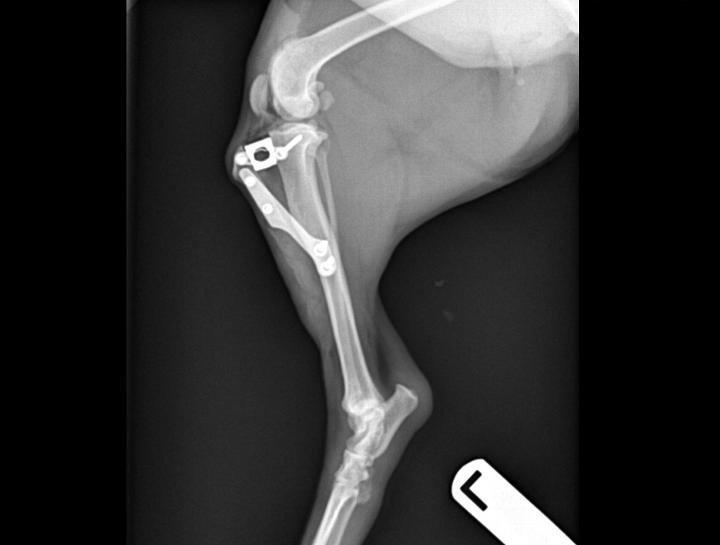

Orthopedic Pet Surgery

Broken and fractured bone repair.